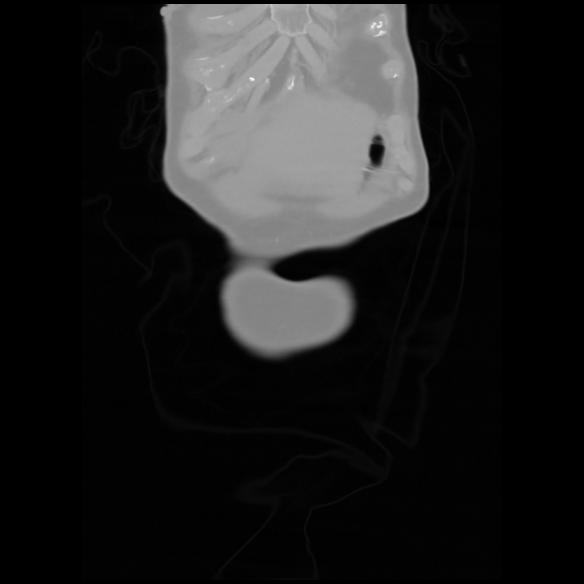

6 CUERPO,CE,Coronal,3.000,CUERPO,Coronal,